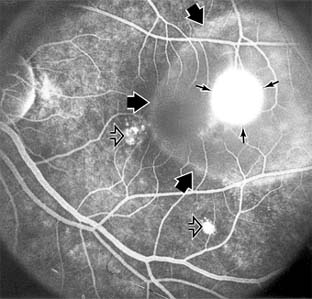

Presumed Ocular Histoplasmosis Syndrome (Figures 10-5, 10-6 and 10-7)

In this disease, serous and hemorrhagic detachments of the macula are associated with multiple peripheral atrophic chorioretinal scars and peripapillary chorioretinal scarring (see Chapter 7). The syndrome usually occurs in healthy patients between the third and sixth decades of life, and the scars are probably caused by an antecedent subclinical systemic infection with Histoplasma capsulatum. The macular detachments are due to subretinal neovascularization, and the visual prognosis depends on the proximity of the neovascular membrane to the center of the fovea. If the membrane extends inside the foveal avascular zone, only 15% of eyes will retain 20/40 vision. A macular scar may change over time, and 10% of patients with normal maculae will develop new atrophic scars in this region. The relative risk of developing macular subretinal neovascularization in the second eye of an affected patient is significant, and these patients should be instructed in the frequent use of the Amsler grid and the importance of prompt examination when changes are detected.

Figure 10-5

Figure 10-5: Presumed ocular histoplasmosis syndrome with active disease (large arrows) and an inactive pigmented macular scar (small arrow). Peripapillary pigmentation (curved arrow) is also present.

Figure 10-6

Figure 10-6: The early fluorescein angiogram shows an inactive hypofluorescent scar (small arrow) and the characteristic lacy hyperfluorescence of subretinal neovascularization (open arrows).

Figure 10-7

Figure 10-7: Late fluorescein leakage from macular subretinal neovascularization in a patient with presumed ocular histoplasmosis syndrome.

Argon laser photocoagulation of a subretinal neovascular membrane outside the foveal avascular zone in symptomatic patients is of value in preventing severe vision loss. The surgical removal of submacular membranes may prove useful in preserving vision.